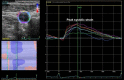

Methods: This study was a prospective study including 48 statin-naïve patients (age, 58.2±8.4 years; 29.2% male) with hypercholesterolemia. Circumferential carotid artery strain (CAS) and stiffness index (β2) were measured using speckle-tracking imaging before and after 3 months of high-dose pitavastatin treatment (4 mg daily). For the comparison, we measured conventional carotid elasticity parameters and intima-media thickness using B-mode ultrasound at the same time points.

Results: Compared with baseline, there was significant improvement in circumferential CAS (2.98%±1.18% to 3.40%±1.43%, p=0.008) and β2 (0.19±0.07 to 0.17±0.08, p=0.047) after statin therapy. Contrariwise, there were no significant changes in all conventional carotid elasticity metrics and intima-media thickness. When stratifying patients into two subgroups by 10 year atherosclerotic cardiovascular disease (ASCVD) risk, speckle-tracking-derived circumferential CAS and β2 improved significantly only in patients with ASCVD risk ≥ 7.5%.

Conclusions: Short-term treatment with high-dose pitavastatin improved carotid artery elasticity measured by speckle-tracking method, but not conventional parameters by B-mode ultrasound. Speckle-tracking-based measurements may allow the early noninvasive assessment of statin effects on vascular function in hypercholesterolemic patients.